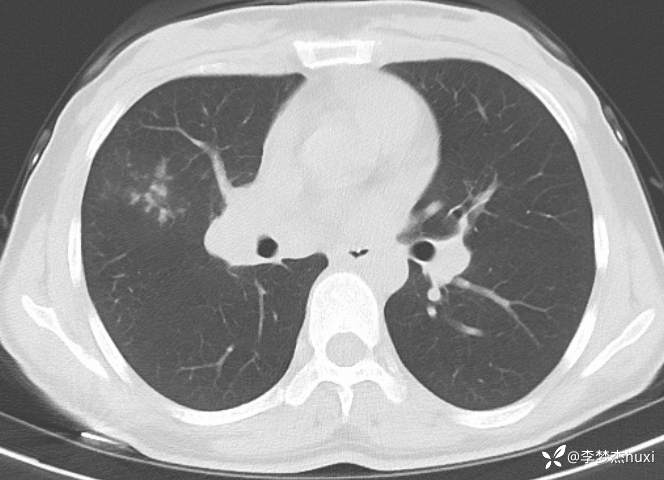

女性35岁,主因咳嗽、咳痰1月,胸部CT报肺炎,猜对乃神医!

女, 35 岁,主因咳嗽、咳痰1月于2025-11-05 08:46入院。

1.现病史:患者中年 女,患者于入院前1月“感冒”后出现咳嗽、咳痰,为黄白痰,不易咳出,无痰中带血,咽部刺痒不适,咳嗽明显,无胸痛,无胸闷、憋气,无恶心,未呕吐,无腹痛、腹泻,无尿频、尿急、尿痛,于院外口服药物(具体不详)治疗,病情未见好转,2025-11-4于我院门诊查胸部CT提示右肺炎症。为进一步诊治来我院;门诊以“肺炎”收入院 。

肺炎。